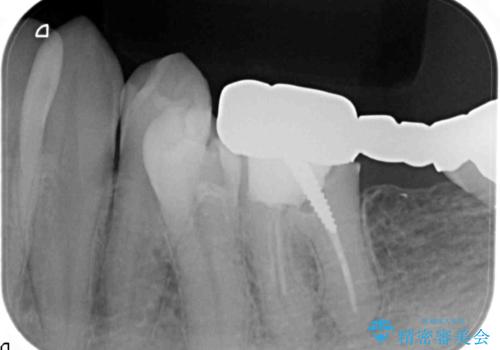

左下には親知らずを支台とした設計に無理のあるブリッジが装着されており、根管治療も不十分な状態です。

清掃性の悪いブリッジ・親知らずを除去し再根管治療・インプラントを含めた咬合再構成の計画を立てます。